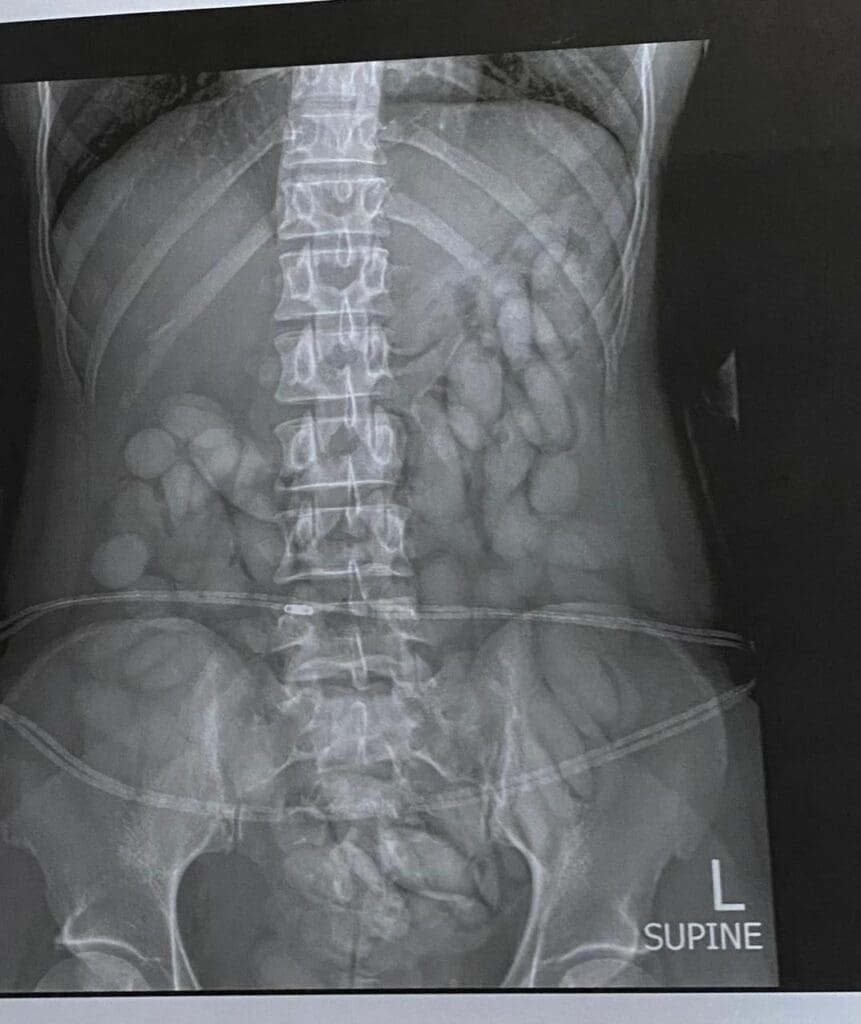

She was immediately arrested, taken to a local hospital where a medical x-ray confirmed and detected foreign objects in her stomach. The process to release the suspected drugs from her body is underway. She has already released more than 60 bullets of suspected cocaine thus far.